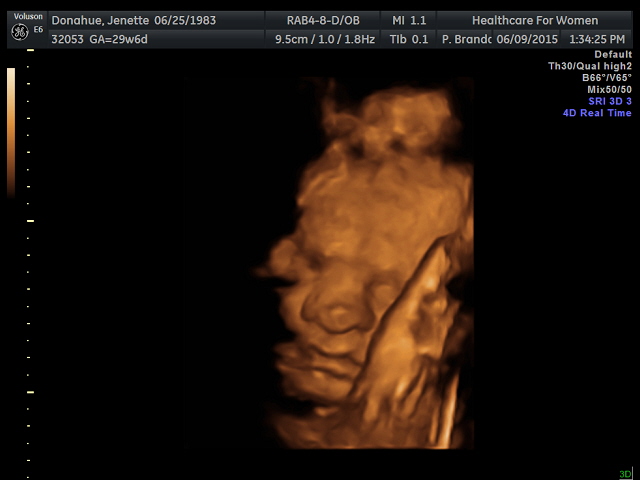

Share your 3D pics!!!!